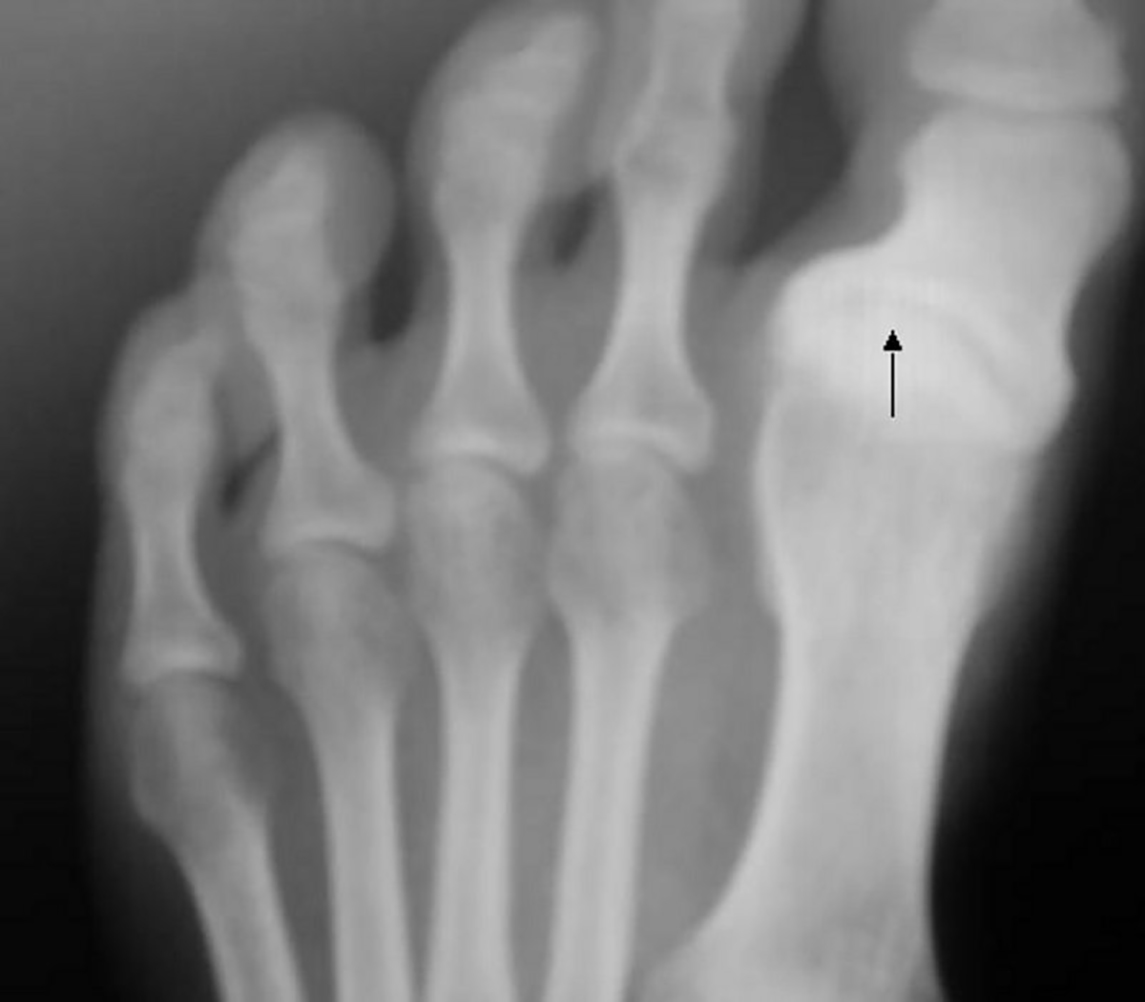

Hallux varus, or sandal gap,[1] is a deformity of the great toe joint where the hallux is deviated medially (towards the midline of the body) away from the first metatarsal bone. The hallux usually moves in the transverse plane. Unlike hallux valgus, also known as hallux abducto valgus or bunion, hallux varus is uncommon in the West but it is common in cultures where the population remains unshod.